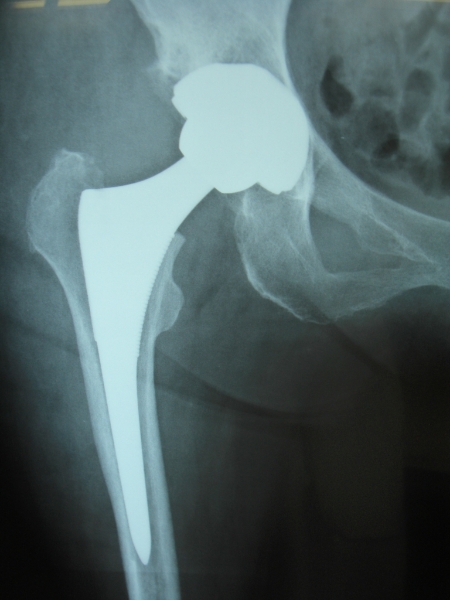

50歳 変形性股関節症 MIS-DAによる人工股関節置換術

術後3日目に歩行訓練開始し術後2週で杖なし歩行で退院

58歳 大腿骨頭壊死 MIS-DAによる右人工股関節置換術

術後2日で離床、3日めに歩行器歩行訓練開始、5日で杖歩行、7日で杖なし歩行可能となり2週で退院

86歳 続発性変形性股関節症 MIS-DAによる右人工股関節置換術

術後3週で杖歩行により退院

変形性股関節症のレントゲン像(A)と骨頭表面(B)および断面(C)、THA術後(D)

大腿骨頭壊死症のレントゲン像(A)と骨頭断面(B)およびTHA術後(C)